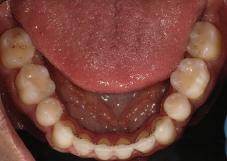

Пациентът постъпи в моята клини ка с наличие на темпоромандибуларен дисфункционален болков синдром, едно странно изместен диск с редукция в дяс ната става, клас II, подклас 2, тесни гор на и долна челюст със струпване, дъл бок овърбайт

орални снимки и снимки на позата, пал пация на мускулите, брукс-чекър, оклу зограми, кондилография, рентгеногра фии, СВСТ и ядрено-магнитен резонанс на темпоромандибуларните стави). Преди началото на ортодонтското лечение всички стари възстановява ния бяха свалени и бяха заменени с дъл госрочни временни от хибридна керами ка. На девитализираните зъби бе прове дено ендодонтско релечение. Индивиду ализиран оклузален сплинт бе направен с цел да се постигне контролирано репо зициониране на долната челюст, като носенето му продължи три месеца до възстановяване на правилната позиция на ставния диск и затихване на орофаци алната болка и дискомфорт в ставата. Брекетите в горната челюст бяха за лепени, за да започне подреждането и нивелирането на зъбите, докато паци ентът все още носеше сплинта. След края на терапията със сплинта бе на правена кондилография, за да се потвър ди триизмерната позиция на долната челюст. След залепване на брекетите в долна

та челюст 4 минивинта (TADs) бяха по ставени в максилата – 2 в небцето и 2 интрарадикуларно във фронта, с цел да се извърши интрузия на цялата зъбна дъга, да се коригира гингивалната усмивка и да се позволи провеждането на обратна на часовниковата стрелка авторо

7Dental Tribune Bulgarian Edition / октомври 2022 г. Преди лечението Фиг. 1 Фиг. 4 Фиг. 7 Фиг. 10 Фиг. 13 Фиг. 16 Фиг. 17 Фиг. 18 Фиг. 19 Фиг. 20 Фиг. 11 Фиг. 14 Фиг. 12 Фиг. 15 Фиг. 8 Фиг. 9 Фиг. 5 Фиг. 6 Фиг. 2 Фиг. 3

8 Dental Tribune Bulgarian Edition / октомври 2022 г. По време на лечението Фиг. 21 Фиг. 25 Фиг. 30 Фиг. 31 Фиг. 34 Фиг. 38 Фиг. 40 Фиг. 44 Фиг. 48 Фиг. 50 Фиг. 49 Фиг. 46 Фиг. 39 Фиг. 41 Фиг. 45 Фиг. 47 Фиг. 42 Фиг. 43 Фиг. 35 Фиг. 36 Фиг. 37 Фиг. 32 Фиг. 33 Фиг. 26 Фиг. 28 Фиг. 29 Фиг. 27 Фиг. 22 Фиг. 23 Фиг. 24